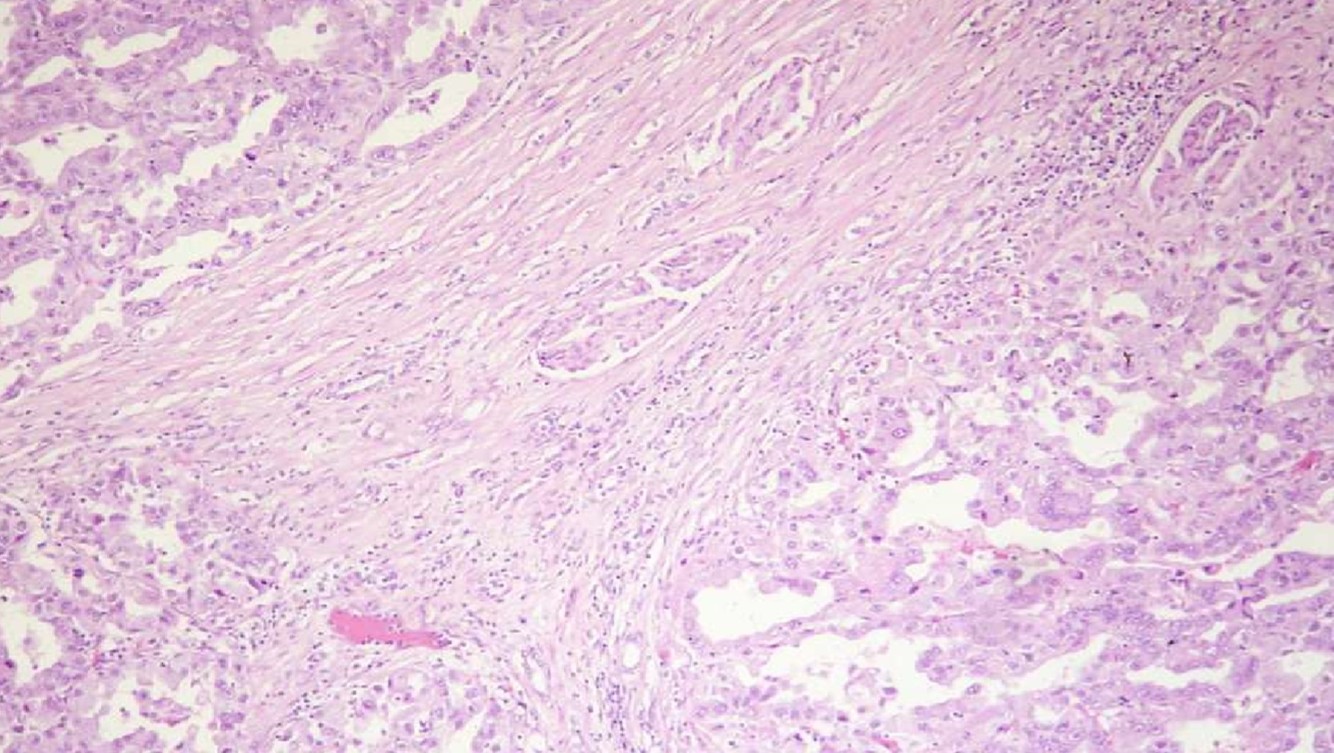

COLLECTING DUCT CARCINOMA

- AKA Bellini duct carcinoma

- Firm mass in medulla

- Infiltrating tubular or tubulopapillary

- Desmoplastic stroma

- +/- cytoplasmic and intraluminal mucin

- High grade

- Poor prognosis

- Rule out met

- (+) E-cadherin, PAX8, L&Hmw CK (var)

- (-) AMACR, racemase, CD10, CK20